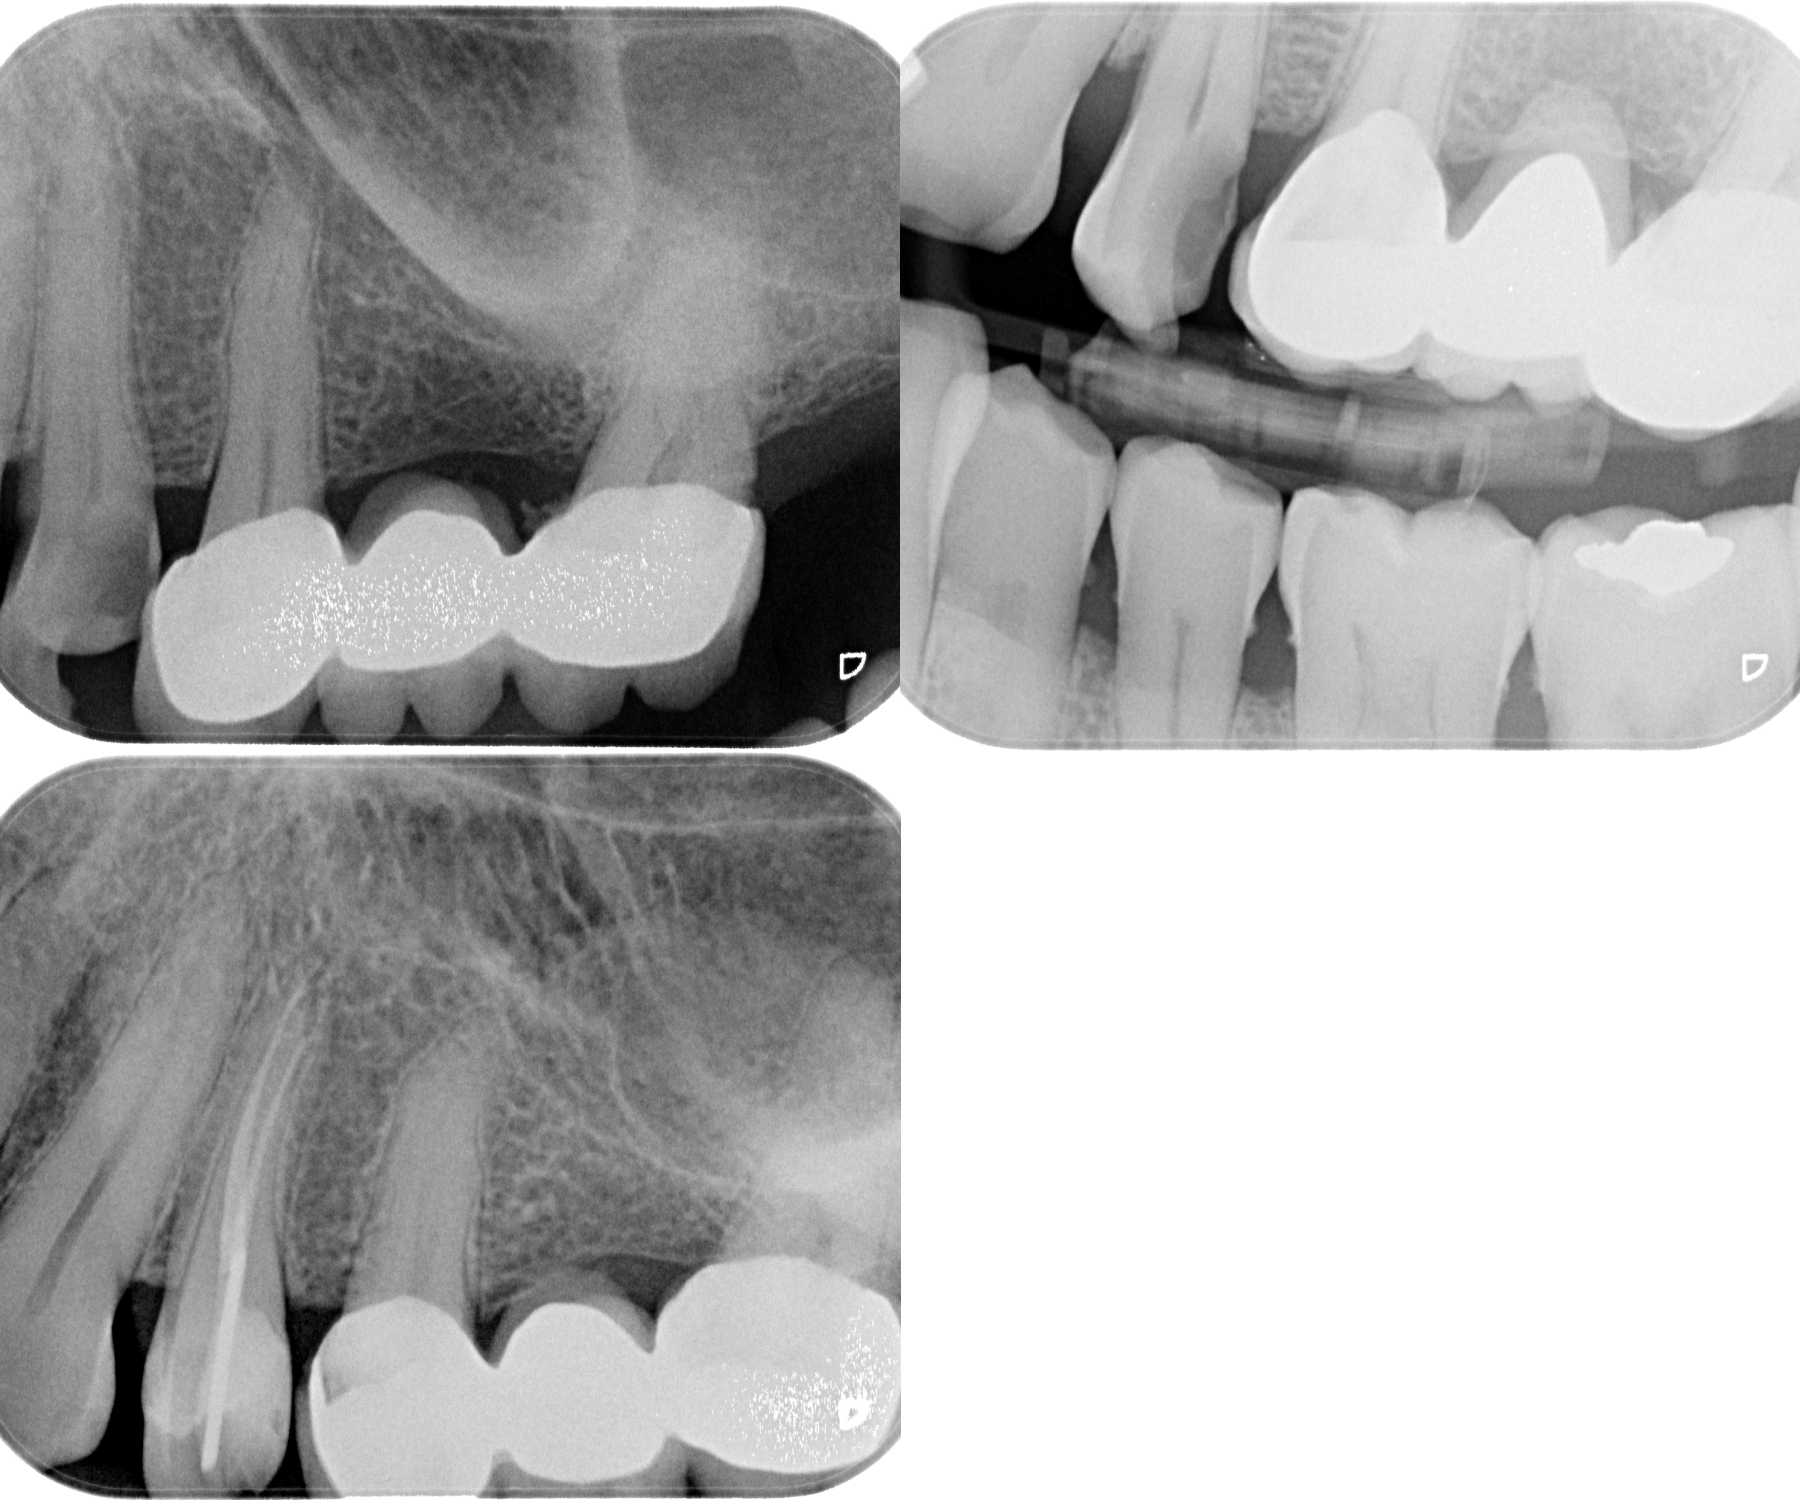

Routine RCT

Revathi Miglani

August 27, 2018

Cases